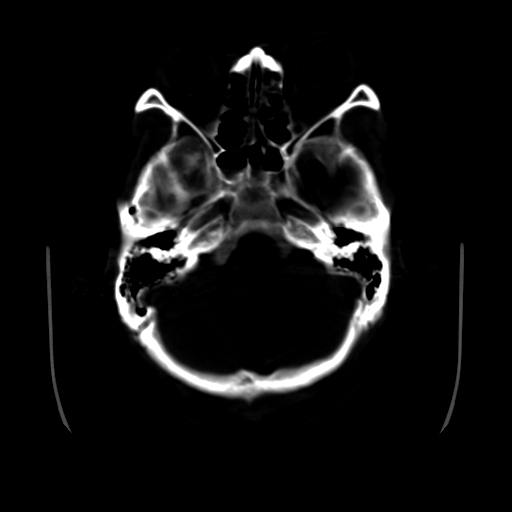

标题: CT25225:男,51岁,头外伤一小时。 [打印本页]

标题: CT25225:男,51岁,头外伤一小时。

男,51岁,头外伤一小时,呕吐两次。

左侧颞部硬膜外;蛛网膜下腔出血 ;脑肿胀

1)左侧中颅窝蝶骨翼后方硬膜外血肿。2)左侧颞顶部硬膜下血肿。3)蛛网膜下腔出血。4)左侧筛窦及双侧蝶窦炎症(或积血)。5)左侧额部头皮软组织肿胀。

1:左侧硬膜外及硬膜下混合血肿。2:蛛网膜下腔出血。3:左额部少量颅内积气?

左颞部硬膜外血肿,蛛网膜下腔出血,副鼻窦积液.头皮损伤.